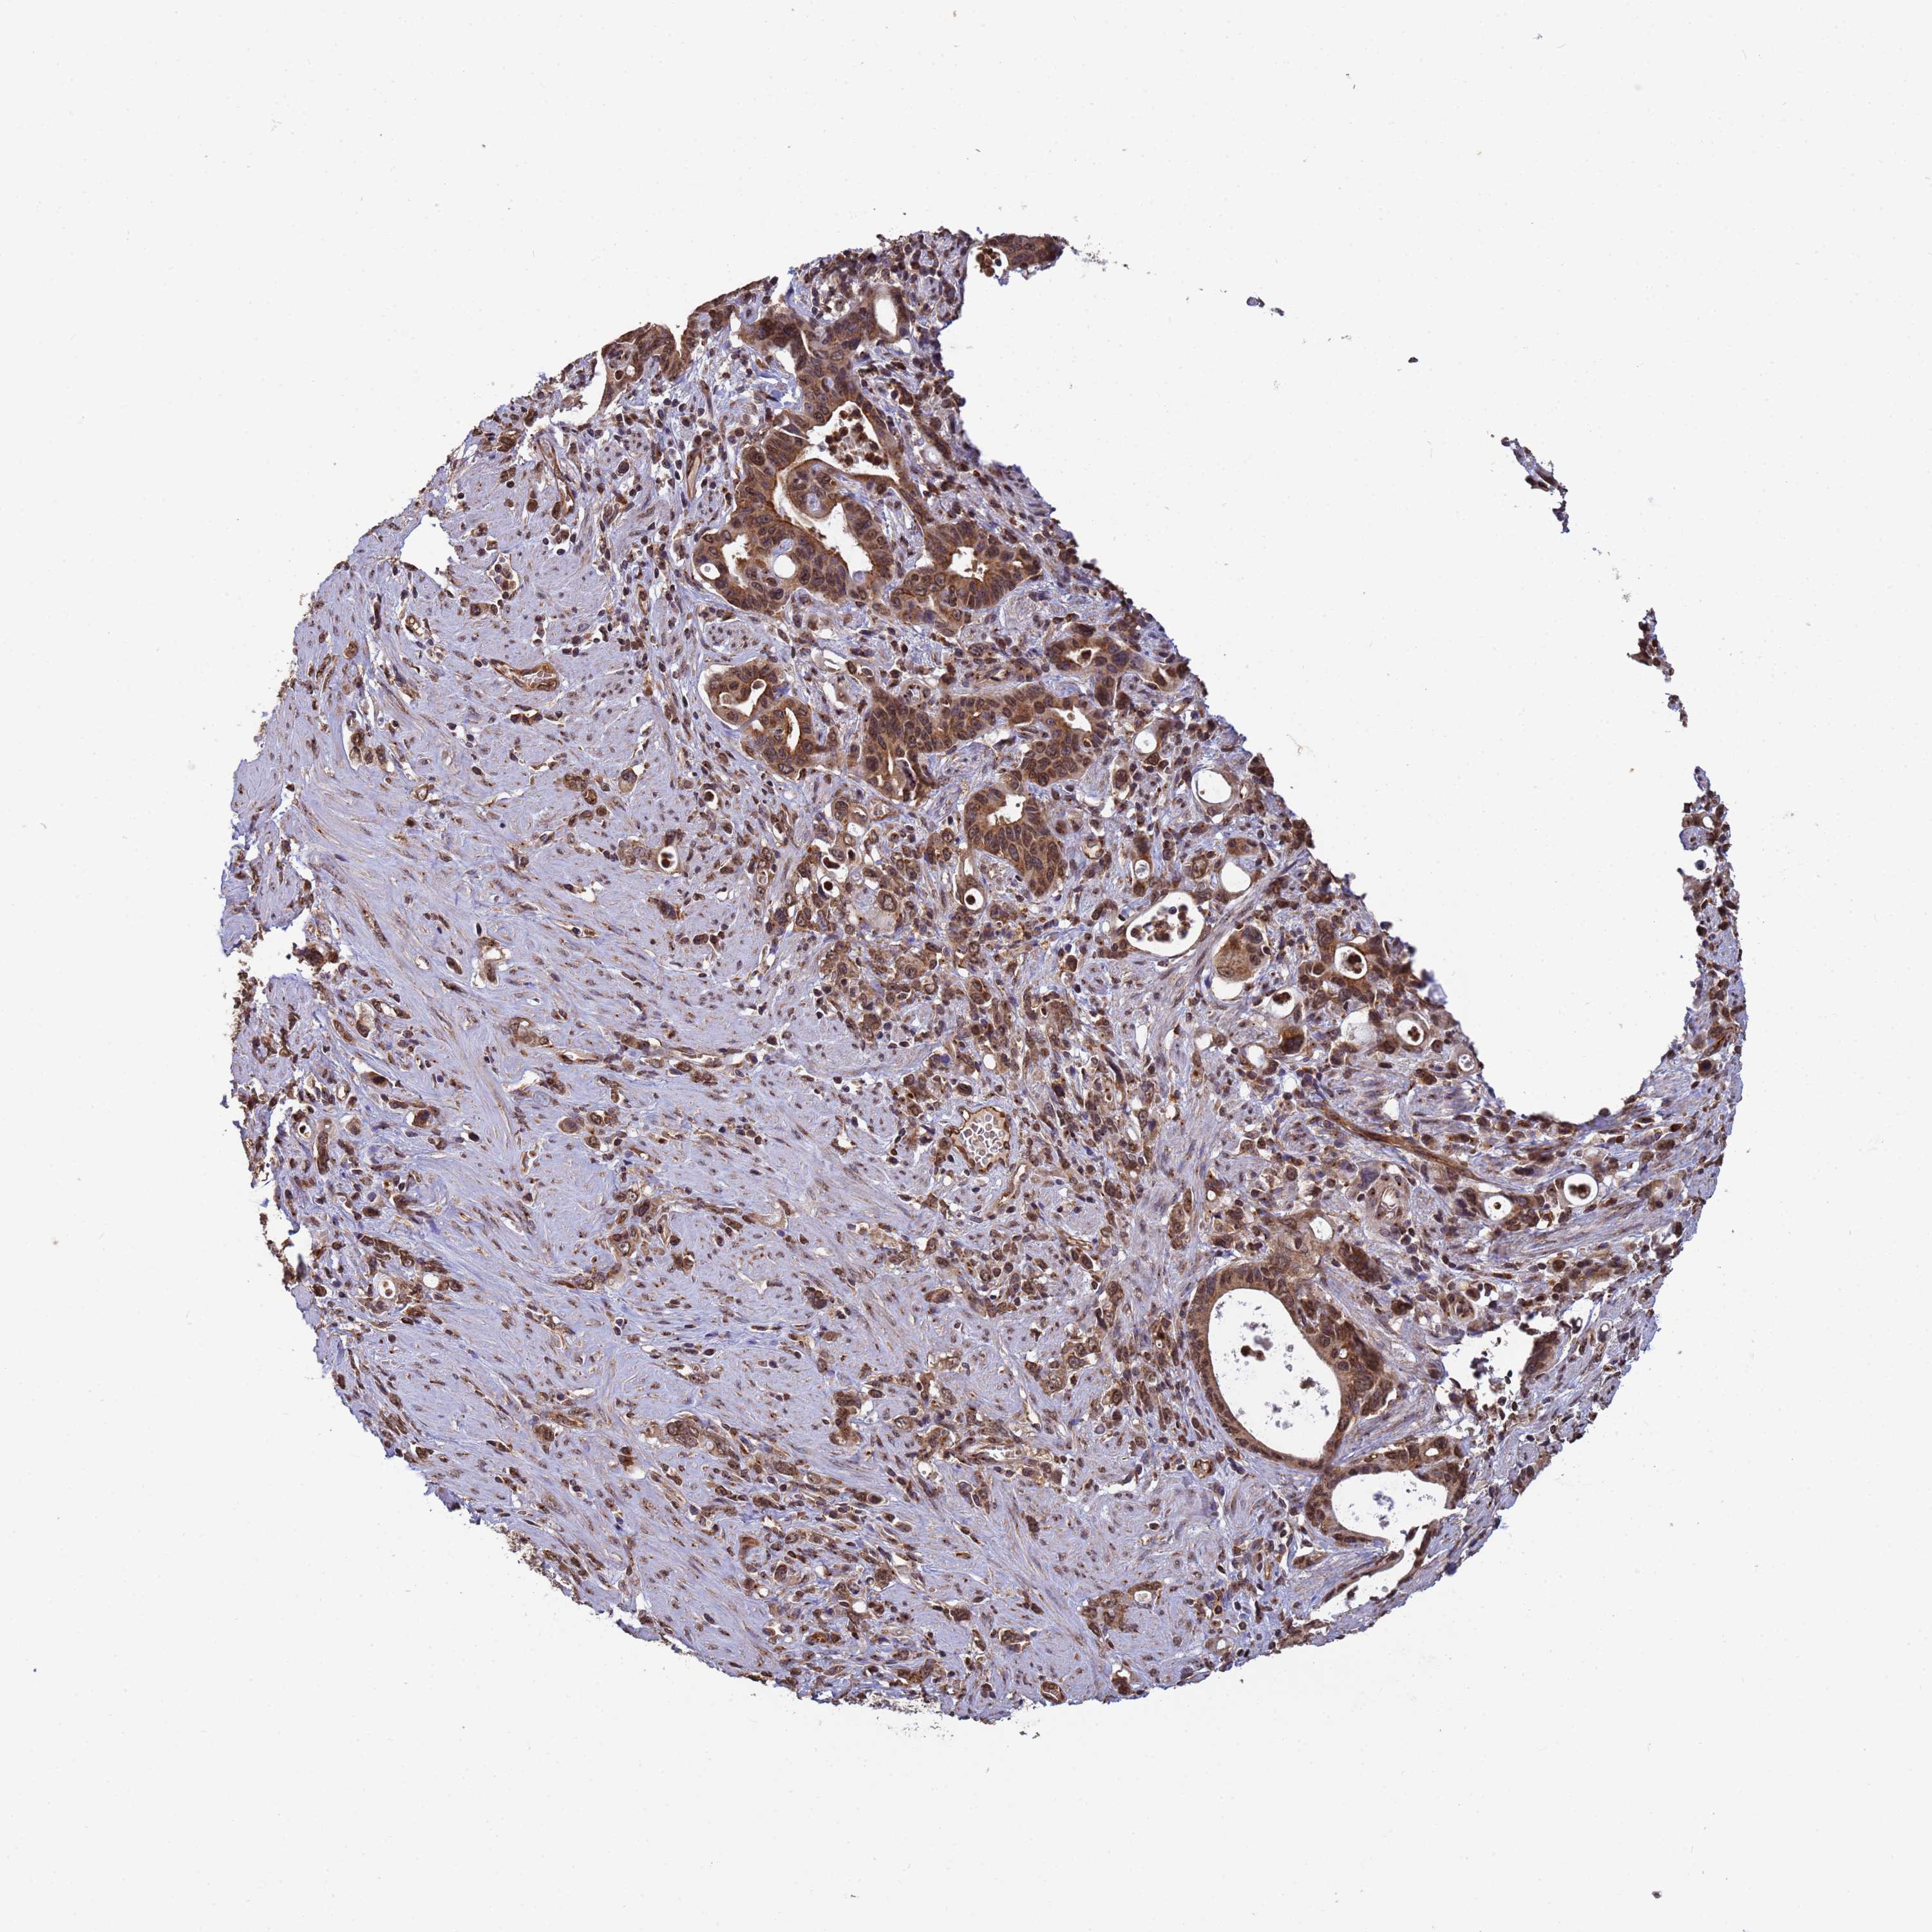

STOMACH CANCER - Protein expressioni

A mouse-over function shows sample information and annotation data. Click on an image to view it in a full screen mode. Samples can be filtered based on level of antibody staining by selecting one or several of the following categories: high, medium, low and not detected. The assay and annotation is described here.

Note that samples used for immunohistochemistry by the Human Protein Atlas do not correspond to samples in the TCGA dataset.

Antibody stainingi

Antibody staining in the annotated cell types in the current human tissue is reported as not detected, low, medium, or high, based on conventional immunohistochemistry profiling in selected tissues. This score is based on the combination of the staining intensity and fraction of stained cells.

Each image is clickable and will lead to virtual microscopy that enables deeper exploration of all samples and also displays staining intensity scores, fraction scores and subcellular localization as well as patient and tissue information for each sample.

Antibody HPA045624

Staining

High

Medium

Low

Not detected

Intensity

Strong

Moderate

Weak

Negative

Quantity

>75%

75%-25%

<25%

None

Location

Nuclear

Cytoplasmic/membranous

Cytoplasmic/membranous,nuclear

Adenocarcinoma, NOS